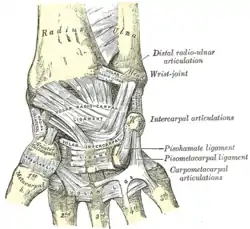

The midcarpal joint is the S-shaped joint space separating the proximal and distal rows of carpal bones. The intercarpal joints, between the bones of each row, are strengthened by the radiate carpal and pisohamate ligaments and the palmar, interosseous, and dorsal intercarpal ligaments. Some degree of mobility is possible between the bones of the proximal row while the bones of the distal row are connected to each other and to the metacarpal bones —at the carpometacarpal joints— by strong ligaments —the pisometacarpal and palmar and dorsal carpometacarpal ligament— that makes a functional entity of these bones. Additionally, the joints between the bases of the metacarpal bones —the intermetacarpal articulations— are strengthened by dorsal, interosseous, and palmar intermetacarpal ligaments.[6]

Wrist joint. Deep dissection. Posterior view.

Wrist joint. Deep dissection. Posterior view. Wrist joint. Deep dissection. Posterior view.

Wrist joint. Deep dissection. Posterior view. Wrist joint. Deep dissection.Anterior, palmar, view.